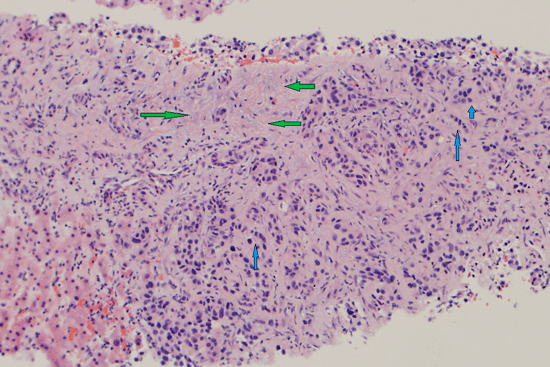

Выполнение резекции ретропеченочного отде-ла НПВ потребовалось 3-му и 4-му пациентам (табл. 2). Таблица 2. Послеоперационные осложнения, данные гистологического патоморфологического исследования и статус краев резекции у пациентов, перенесших обширные резекции печени и резекции сосудов Ввиду нетолерантности к пережатию НПВ ее протезирование 3-му пациенту осуществлено в условиях обходного вено-венозного шунтирования. В данном случае НПВ замещена сосудистым протезом из политетрафторэтилена диаметром 30 мм и длиной 80 мм (см. рис. 2). Рис. 2 . Вид операционной раны после удаления препарата и протезирования НПВ. НПВ ― нижняя полая вена. Выполне-на радиочастотная абляция сателлитного очага S2 печени.